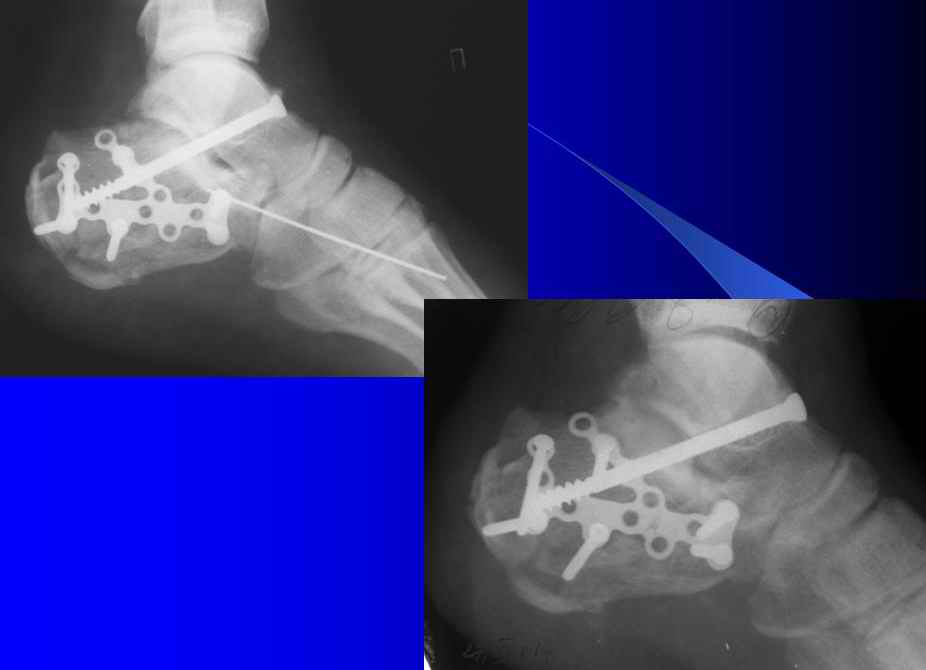

Результат посылаю отдельно.На предыдущих рент. видна репозиция.

Справа ситуация сложнее так как имеется помимо перелома имеется вывих тела пяточной костиПоэтому даже если удастся достигнуть хорошей репозиции необходимо сделать первичный подтаранный артродез.Иначе кость не будет держать в своём ложе.Но пластина нужна обязательно чтобы восстановить форму пятки.С уважением Дрягин

Otkritaya repositsija, fixatija plastinoj. Sprava podtaranniy artrodez.